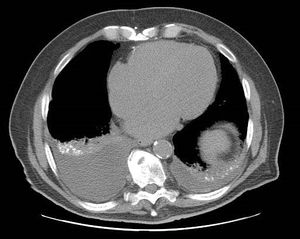

A CT image of aspiration pneumonia, a common cause of death in HD

وهذا المرض ليس له علاج، وإن كان كثير من أعراضه يمكن تخفيفها عن طريق الأدوية والطرق العلاجية الأخرى.